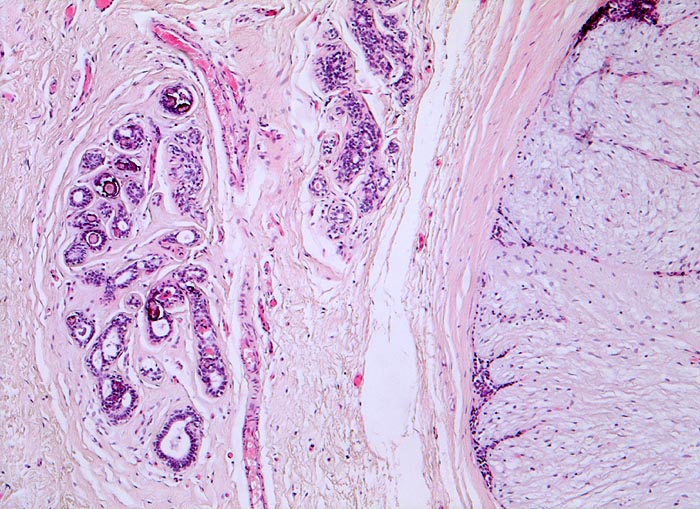

• Biphasischer organoid aufgebauter Tumor bestehend aus kompaktem zellarmem fibroblastärem Stroma, das in konzentrischen Lamellen um verzweigte, miteinander anastomosierende Drüsenschläuche angeordnet ist.

• Die Drüsenschläuche werden durch das Stroma komprimiert.

• Die Drüsen werden ausgekleidet von einer inneren kubischen bis hochprismatischen Zellschicht und einer äusseren abgeflachten Myoepithelschicht mit klarem Zytoplasma.